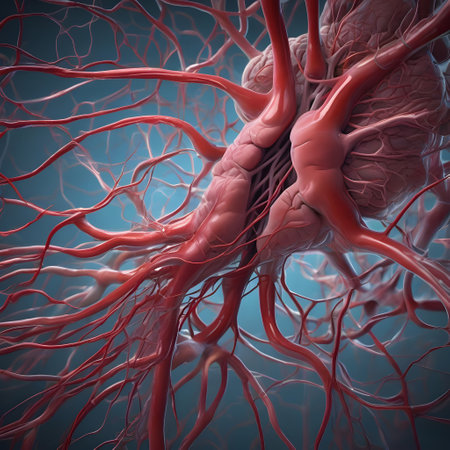

Detailed visuals showcase the complex network of blood vessels in human anatomy.

Blood vessel system and organs in the human body

A detailed view of red blood vessels intertwines across a soft gradient background. The intricate network showcases the complexity of human circulation highlighting the various sizes and shapes of the vessels

Blood vessel system and organs in the human body

Blood vessel system and organs in the human body

Blood vessel system and organs in the human body

Blood vessel system and organs in the human body

Blood vessel system and organs in the human body

Detailed perspective of blood vessels filled with bright red cells on a twisted, dark background. The intricate network highlights the beauty of biological structures.

Human blood veins, red vessels

On a microscopic scale we can observe the intricate process of angiogenesis as new vessels form and weave through tissue to deliver vital nutrients

blood vessels. circulation system. Veins and arteries. Generative AI

Blood vessel system and organs in the human body